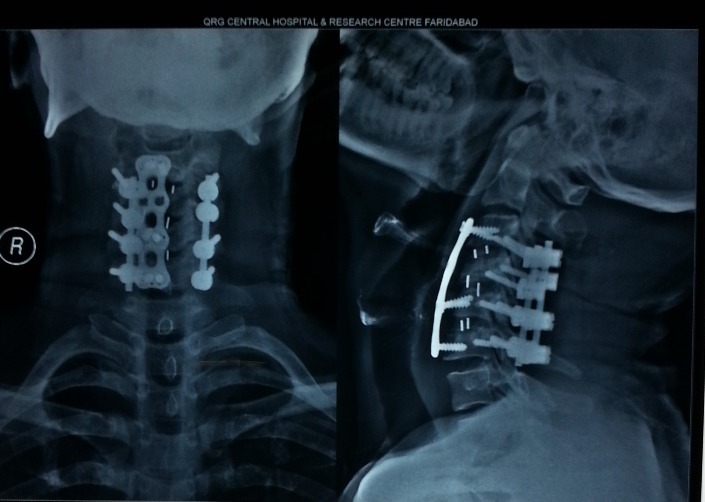

CERVICAL SPINE SURGERY

cervical

Anterior and Posterior cervical fixation.